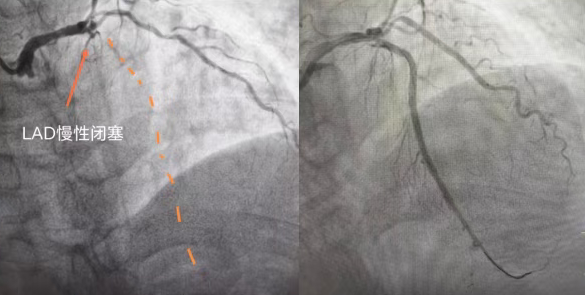

74 歲的陳阿姨(化名),數(shù)月來(lái)被反復(fù)胸痛折磨的寢食難安,稍一活動(dòng)就胸口憋悶、刺痛難忍,休息后也難徹底緩解。輾轉(zhuǎn)就醫(yī)后,病情始終未獲有效解決,最終在國(guó)文醫(yī)院迎來(lái)轉(zhuǎn)機(jī):檢查顯示其心臟前降支近端鈣化并完全閉塞,屬于冠心病中難度極高的冠狀動(dòng)脈慢性完全閉塞病變(CTO),堪稱冠脈介入治療的 “最后堡壘”。

心臟正常運(yùn)轉(zhuǎn)依賴冠狀動(dòng)脈供血,前降支作為冠脈中供血范圍最廣、最關(guān)鍵的血管,負(fù)責(zé)心臟前壁、心尖等核心區(qū)域供血,一旦堵塞,極易引發(fā)大面積心肌缺血、急性心梗甚至猝死。這位老年女性所患的CTO病變,即冠脈完全閉塞超3個(gè)月,血管壁伴隨大量堅(jiān)硬鈣化斑塊,如同心臟“生命干道”被石塊堵死,管壁脆硬。

手術(shù)由北京專家全程主導(dǎo),操作精準(zhǔn)細(xì)致,成功打通閉塞前降支,徹底解決老人心肌缺血問(wèn)題。術(shù)后第二天,老人精神明顯好轉(zhuǎn),可下地活動(dòng),家屬對(duì)專家技術(shù)與醫(yī)院服務(wù)充滿感激。